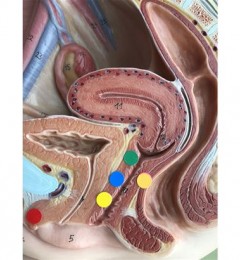

舌系带是位于舌头下方的带状或片状结构,舌系带过短、过紧或舌头几乎完全黏固于口腔底部是婴儿出生时的一种病症。某些时候,这种过紧的情形也可能发生上唇和牙龈之间的上唇系带。这样的情况可能导致母乳哺喂困难,在极少数情况下,也可能影响儿童的牙齿健康或说话。

母乳被认为是新生儿喂养的首选,但若发生母乳哺喂困难时,例如宝宝无法顺利含住乳头、或母亲觉得太过疼痛,父母可能会得到透过手术修剪婴儿上唇系带或舌系带的建议,称为系带切开术,以帮助婴儿顺利含住乳头。

跨科别医学团队对115名已准备进行上唇系带或/和舌系带切开手术的新生儿进行全面的检查与喂养评估,包括临床病史、口腔检查和母乳喂养观察等。医学团队提供实时的建议和策略,解决母乳喂养时遇到的困难。